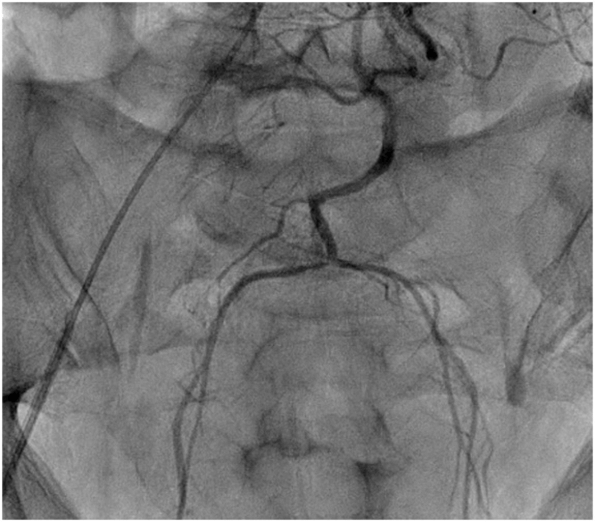

A 45-year-old gentleman, an advocate, with no prior comorbid illness, presented to emergency room of our hospital at 9pm with complaints of abdominal pain and distension, unable to void urine/defecate. On examination, he was pale, hypotensive, diaphoretic, had tachycardia and tachypnoea. Abdomen was tender and distended, predominantly lower abdomen. Rectal examination revealed a bulge over anterior rectal wall and there was no significant rectal bleed. He had undergone DGHAL RAR that morning elsewhere at 11am and his symptoms began 2 hrs after surgery. There was no history of abdominal or pelvic trauma. There was no prior history of hemorrhagic diathesis (petechiae/bleed after minor trauma/spontaneous bleeds), and coagulation studies were in normal range. Blood investigations revealed a Haemoglobin of 5gm%, which was 15 gm% in the test done before surgery the same morning. CECT abdomen revealed a large pelvic hematoma with no active contrast extravasation (Figure 1). He continued to worsen, requiring greater pressor dose, increasing abdominal distension and fall in haemoglobin. He was taken for emergency embolization of bleeder but, no contrast leak was identified (Figure 2). He was taken up for emergency laparotomy.

Figure 2: IMA angiogram – No contrast leak.